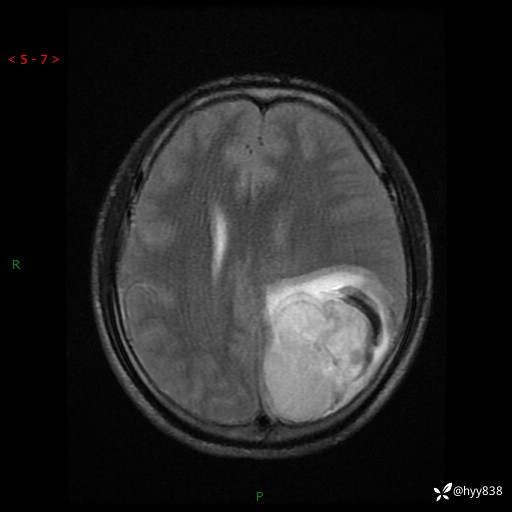

病例年轻小伙,头痛伴呕吐半年,渐进性加重1月。疑难病例,第一次见--结果公布~

性别:男

年龄:21岁

简要病史:头痛伴呕吐半年,渐进性加重1月

颅脑MRI平扫+增强